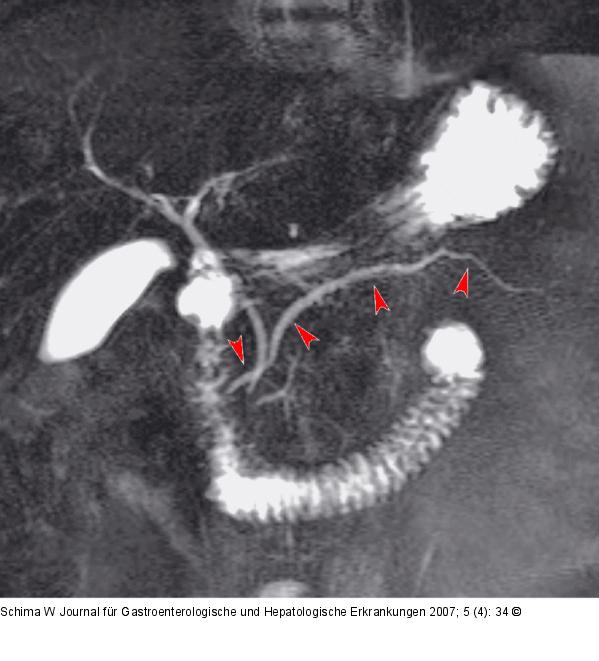

Abbildung 1b: Ductus pancreaticus Die Secretin-MRCP zeigt den nunmehr dilatierten D. pancreaticus major, der nicht gemeinsam mit dem D. choledochus mündet, viel besser: Diagnose eines Pancreas divisum. Der kleine D. Wirsungianus im Pankreaskopf, der gemeinsam mit dem D. choledochus an der Papilla major mündet, ist nun auch gefüllt. |

Die Secretin-MRCP zeigt den nunmehr dilatierten D. pancreaticus major, der nicht gemeinsam mit dem D. choledochus mündet, viel besser: Diagnose eines Pancreas divisum. Der kleine D. Wirsungianus im Pankreaskopf, der gemeinsam mit dem D. choledochus an der Papilla major mündet, ist nun auch gefüllt. |